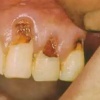

Pöördumatu hambanärvi põletik

Kui algul lihtsalt külmatundlik olnud hammas hakkab valutama järjest tugevamini, siis on tavaliselt tegemist hambanärvi pöördumatu põletiku ehk pulpiidiga.